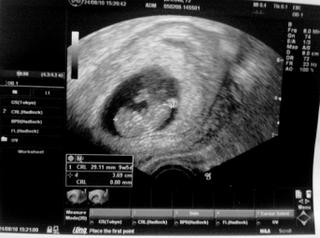

já měla dnes kontrolu,mimísek odpovídá podle měření 9+5 ,pořádně se mrskal,natahoval se ,mával ručičkama-je to divoch,m 😀 udr ho nemohl ani změřit,musela sem chvilku ležet jestli se neuklidní ,UTZ přes břicho to nešlo vůbec,pořád někam plaval , 😀 tak to muselo jít vnitřně ,i tak sebou pořád šil